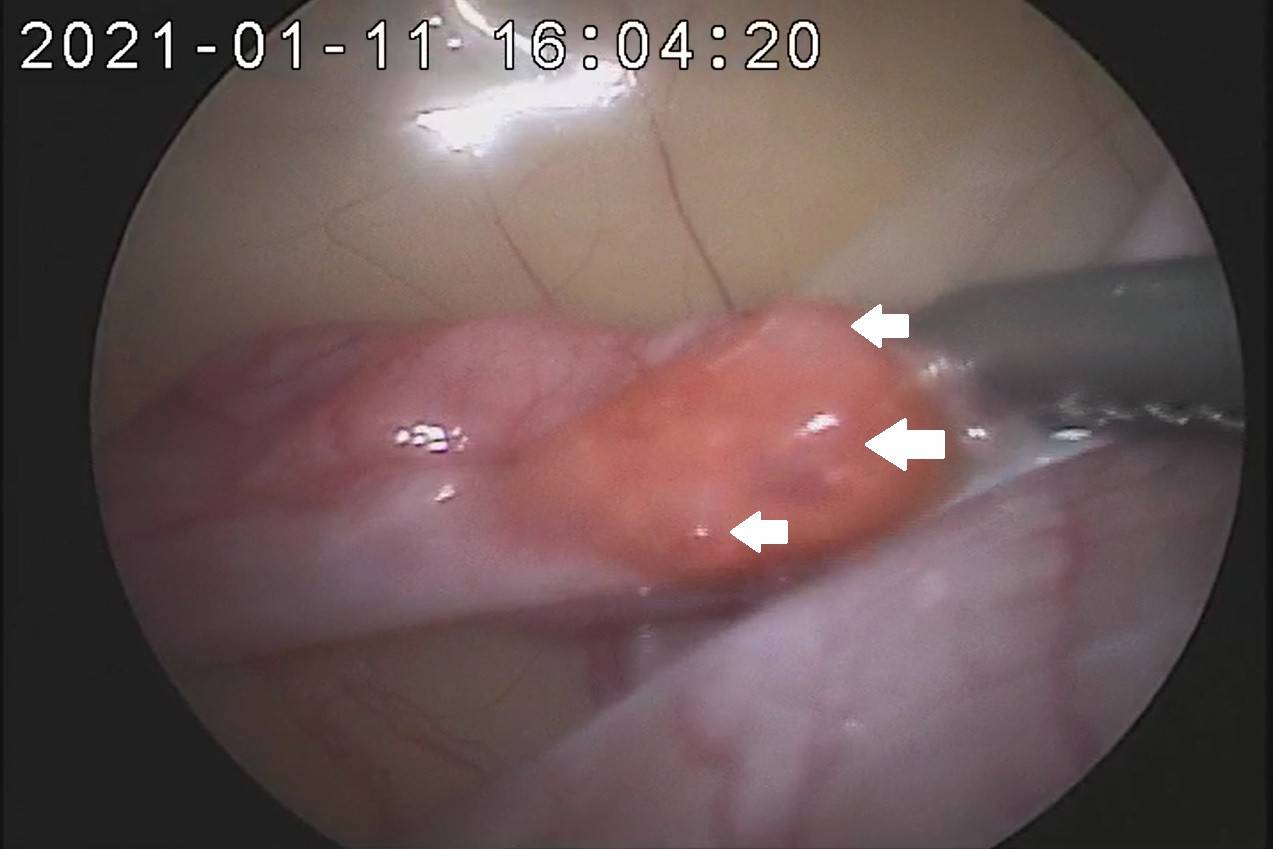

卵管を傷つけないように慎重に注入器の先端を卵管内に挿入します。卵管の直径は1mm程度なので繊細な技術が必要です。挿入できたら精子を注入して人工授精は終了です。実際の注入は左右合わせて数分で終了します。

精子を注入した際の腹腔鏡の画像はこちらです。